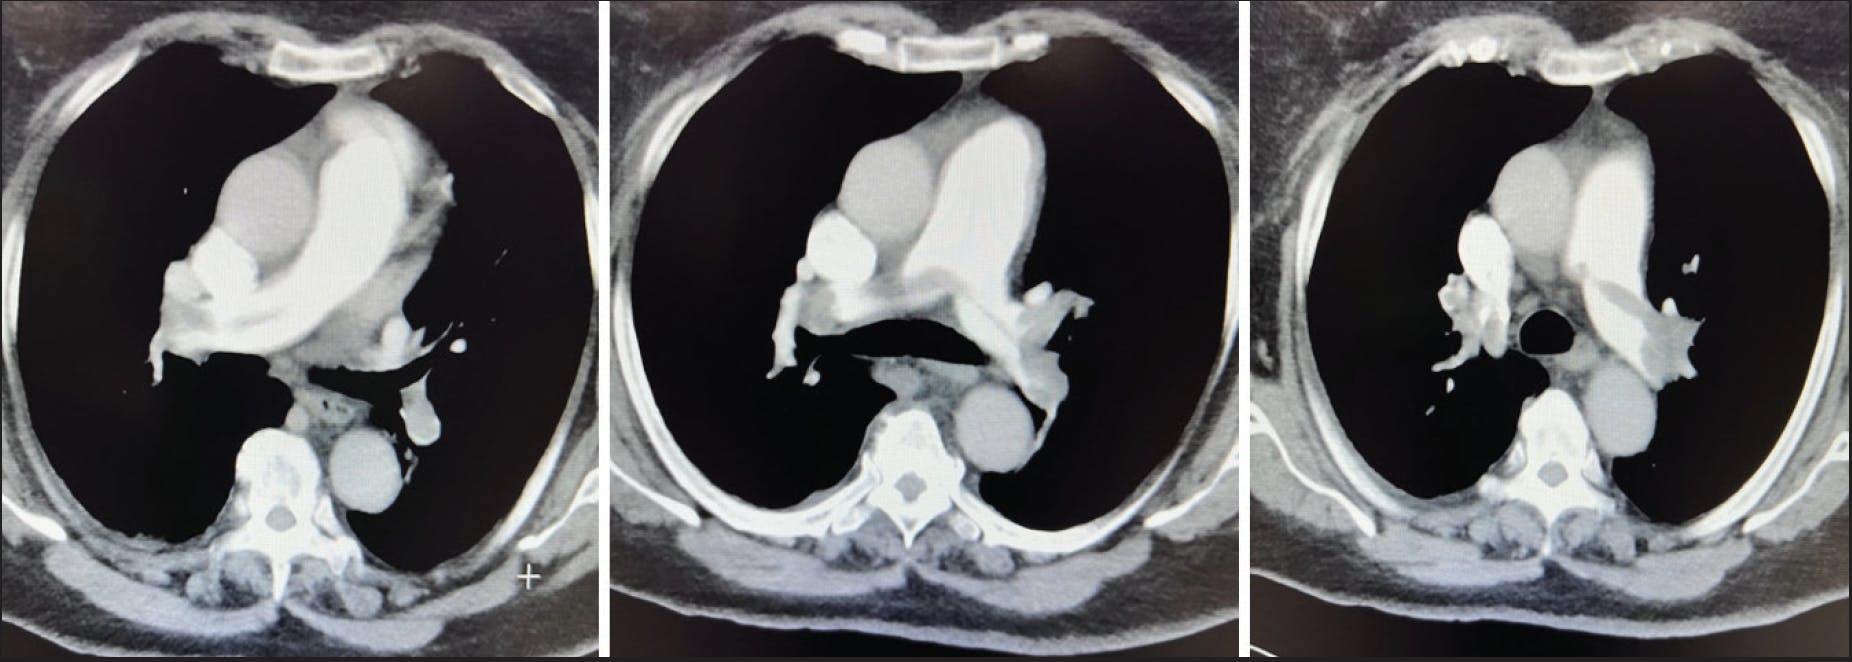

In the emergency department, she was tachycardic at 120 bpm with a systolic blood pressure of 100 mm Hg. She required 40% high-velocity oxygen support and was assessed as clinically unstable. Echocardiography revealed a hyperdynamic left ventricle, a dilated right ventricle with moderately to severely reduced function, and McConnell sign, consistent with PE (Figure 1). CTA showed a high RV/LV ratio of 1.4 and extensive left PE with possible saddle thrombus (Figure 2). The patient became progressively unstable and was administered thrombolytic therapy with tissue plasminogen activator. Overnight, her oxygen requirement improved to 6 L via nasal cannula, although she remained dyspneic and relatively hypotensive. Intravenous heparin was continued, and she was referred to interventional cardiology for further management with CAVT using Penumbra’s Lightning Flash 2.0.

Figure 2. CT revealing high RV/LV ratio of 1.4 and extensive PE with saddle thrombus.